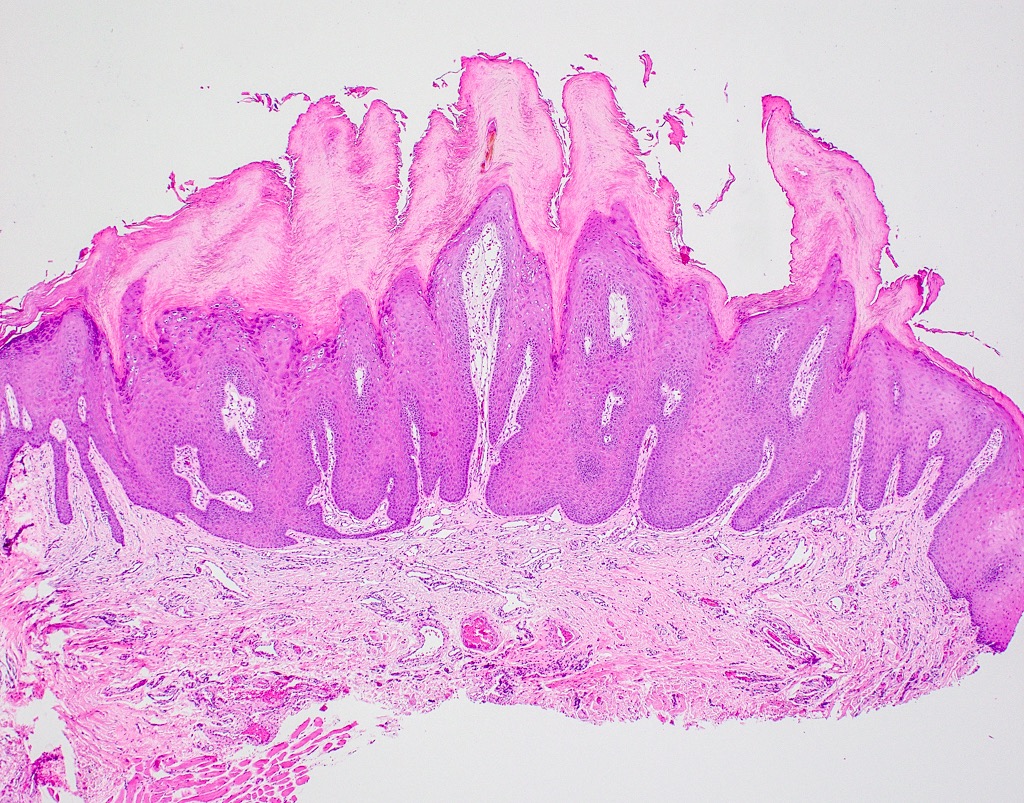

- Similar to cutaneous counterpart (Head Neck Pathol 2019;13:80)

- Prominent surface keratinization (often orthokeratin with superficial parakeratin tufts)

- Inward cupping of the rete pegs

- Exophytic / papillary fronds which form church spire-like peaks

- Hypergranulosis with coarse keratohyalin granules and potential eosinophilic intranuclear viral inclusions within the granular cell layer

- Koilocytosis within the superficial epithelial layers

Microscopic (histologic) images

C. Verruca vulgaris. The microscopic images show a well circumscribed, papillary epithelial proliferation with inward cupping of the rete ridges, prominent koilocytosis and prominent keratohyaline granules, which are all features of verruca vulgaris. Answers A and B are incorrect because condyloma acuminatum and squamous papilloma both lack prominent hypergranulosis while condyloma acuminatum exhibits broad, blunted papillary projections rather than the thin, hyperkeratotic projections seen above. Answer D is incorrect because verrucous carcinoma demonstrates broad, pushing rete ridges and lacks circumscription.